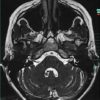

U dây VIII - Ảnh 3

U dây VIII

» Thông tin: Nữ giới – 35 tuổi.

» Lâm sàng: Điếc đột ngột.